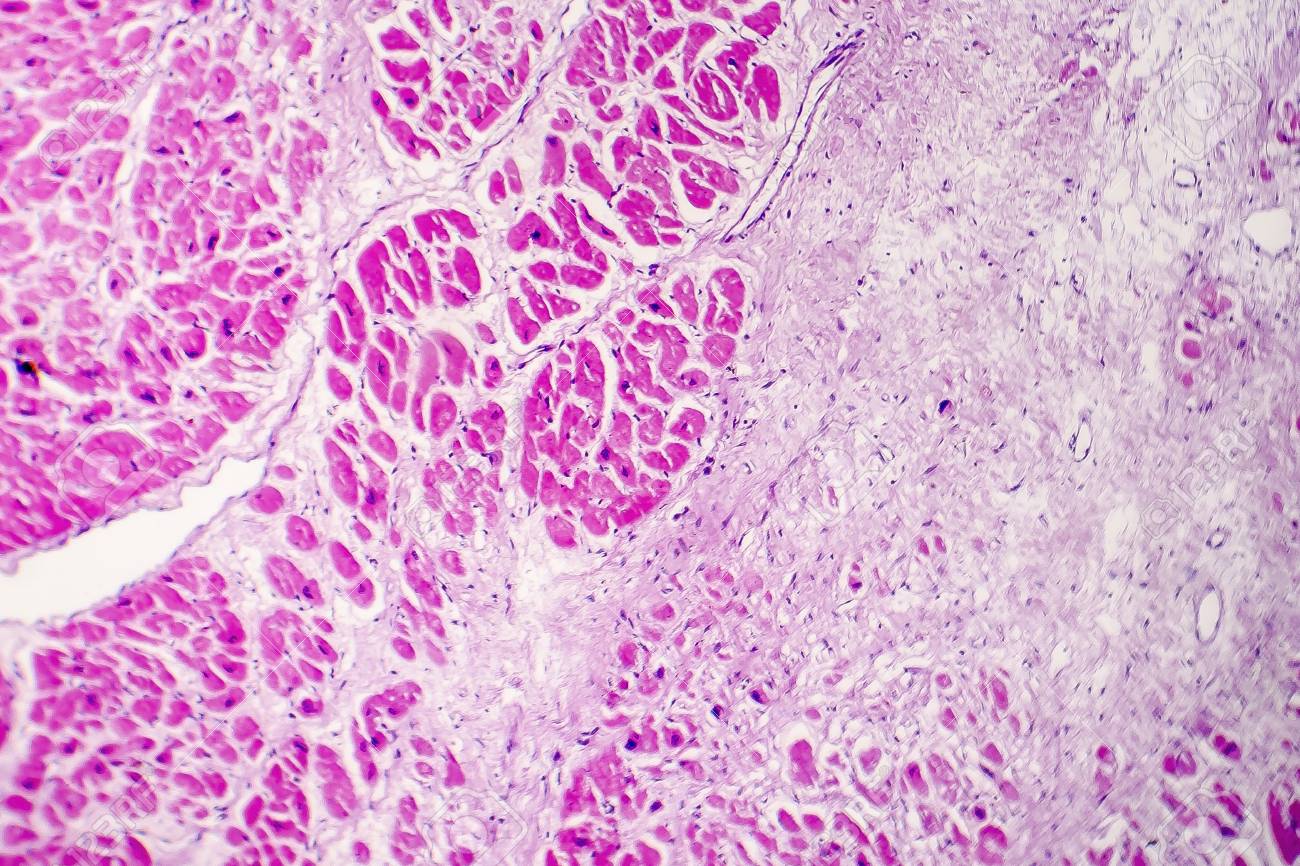

Acute myocardial infarction (AMI) is the consequence of sudden loss of blood supply to myocytes with resultant ischemic necrosis . The histopathologic changes are similar to tissue necrosis at other sites but specific histologic changes depend on stage of infarction .

Myocardial Infarction . Toward the end of the first week, healing of a myocardial infarction becomes more prominent . Seen here is ingrowth of capillaries along with fibroblasts and macrophages filled with hemosiderin . The granulation tissue seen here is found in abundance from 10 days to 3 weeks following onset of infarction , with a peak around . . .